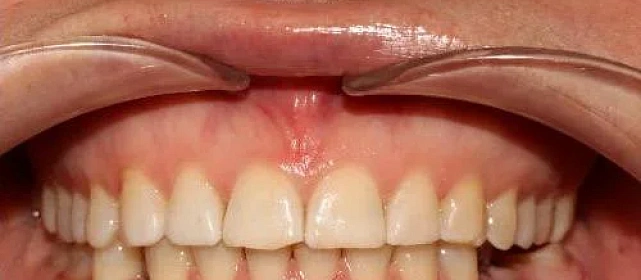

Прикус исправлен, зубы выровнены. Установлены несъёмные ретейнеры на обе челюсти, после установки коронок будут изготовлены ретенционные капы.

Решение: Установили металлические самолигирующие брекеты H4 на обе челюсти. За 28 месяцев выровняли зубы и привели прикус в норму. После снятия брекетов зафиксировали ретейнеры на обе челюсти. Пациентка направлена к ортопеду — в течение недели устанавливает коронки, после чего будет проведено сканирование и изготовлены ретенционные капы уже по окончательному контуру зубов.